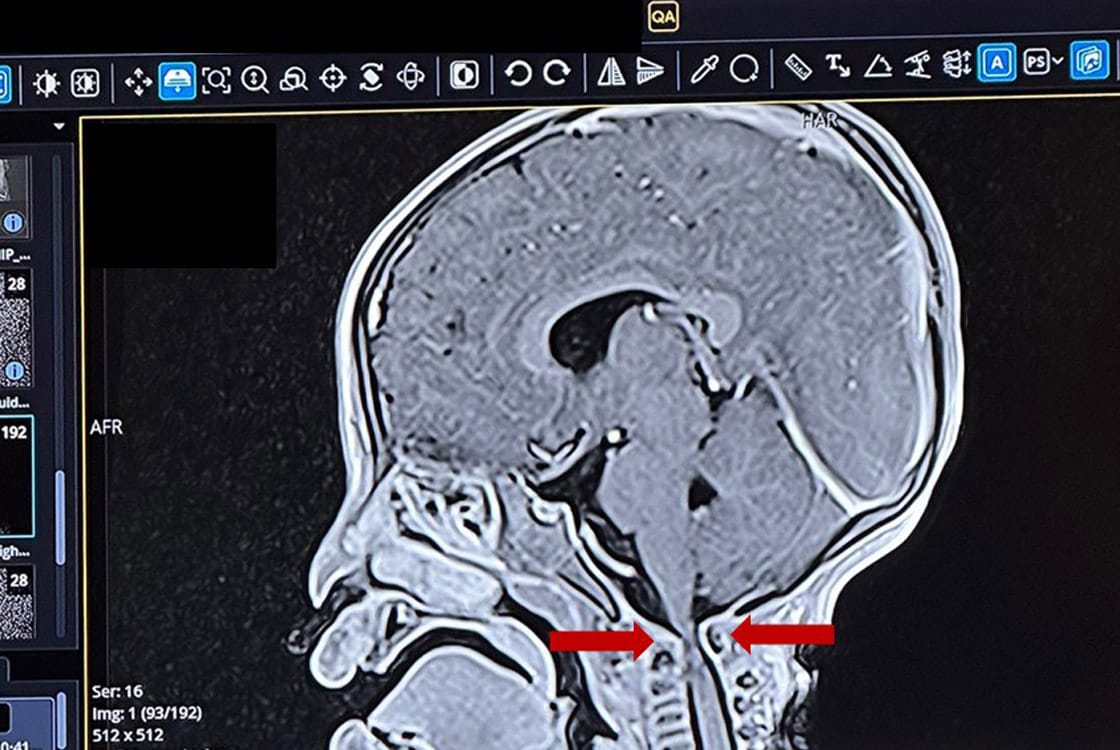

welches Schicksal hinter diesem Bild steckt, ist nicht zu fassen. Emilys Eltern hatten alles versucht. Ärzte konsultiert, Kliniken abgeklappert. Drei Jahre lang. Ihre Tochter kann nicht sitzen. Nicht laufen. Eine schwere Spastik beeinträchtigt alle vier Gliedmaßen. Letzte Woche kam sie zu unserem Kinderarzt Dr. Christian Reibold. Gemeinsam mit Dr. Martina John ordnete er eine MRT-Aufnahme von Kopf und Halsbereich an. Der Befund war eindeutig: Im Bereich des 1. Halswirbels ist das Rückenmark extrem zusammengedrückt. Emily brauchte sofort eine neurochirurgische Operation.

Was war der Grund dafür? Emily kam mit dem Gesicht nach oben zur Welt. Dabei muss es wohl durch eine traumatische Geburt zu einer teilweisen Verrenkung des Kopfes auf der Halswirbelsäule gekommen sein. Drei Jahre lang blieb das unentdeckt.

Unser Neurochirurg Andreas Warkentin trifft erst in der zweiten Jahreshälfte in Peru ein. Er ist dann der einzige im gesamten Bundesstaat Apurímac. Deshalb haben wir Emily nach Cusco verlegt. Drei Jahre lang tappten die Eltern im Dunkeln. Endlich haben sie Klarheit und damit den Weg zur Heilung.